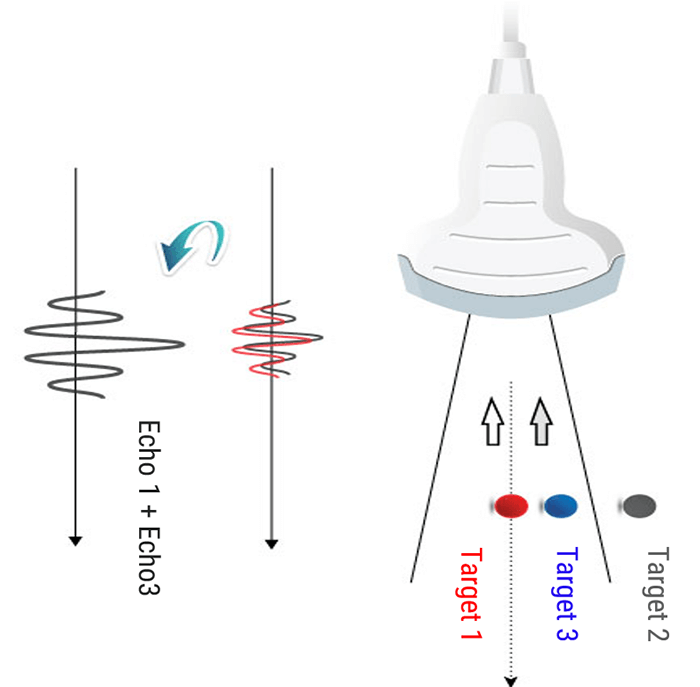

The beam width can be further reduced by adjusting the focal area. It is, therefore, useful to position the target structure in the focal zone to obtain the best possible lateral resolution. The beam diverges increasing its width while propagating in depth. It is possible to focus the ultrasound beam to obtain a narrow beam at the focal length, and thus improve the lateral resolution. Focusing can be accomplished either mechanically, or electronically via a multi-element array.

Electronic Beam Focusing

The focusing of some transducers can be adjusted to a specific depth for each transmitted pulse. The transducer is made up of an array of several piezoelectric elements, rather than a single element compared to the fixed focus transducer. As shown in this animation, the elements are arranged in either a straight, or curved line in the linear array.

Focusing is achieved by not applying the electrical pulses to all of the transducer elements simultaneously. The pulse to each element is passed through an electronic delay The outermost elements will be pulsed first, which produces ultrasound that begins to move away from the transducer. The other elements are then pulsed in sequence, working toward the center of the array.

The centermost element will receive the last pulse. The pulses from the individual elements combine in a constructive manner, to create a curved composite pulse, which will converge on a focal point at some specific distance or depth from the transducer.

The focal depth is determined by the time delay between the electrical pulses. Focal Pulses can be changed electronically to give a good image detail at various depths within the body, rather than just one depth compared to the fixed focus transducer. One approach is to create an image by using a sequence of pulses, each one focused on a different depth or zone within the body.

Another approach is a group of piezoelectric elements that work together to produce the focused beam. Each of the transducers is excited with time offsets. The combination of several focal lengths on transmission improves the quality of the image. In return, the frame rate is decreased by a factor equal to the number of selected focal lengths. And last, the image is reconstructed by zone.